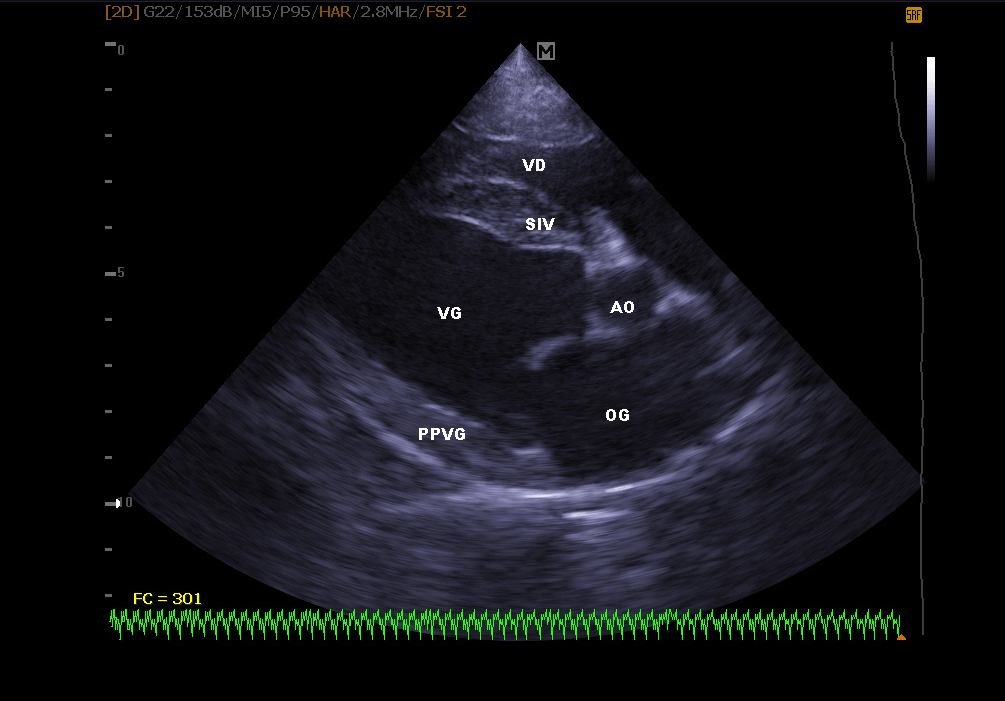

Elle permet de visualiser les différentes parties du cœur (parois, cavités, valvules) et de repérer d’éventuelles anomalies qui empêchent un fonctionnement cardiaque correct . En cas d’insuffisance cardiaque, l’échocardiographie permet aussi un suivi régulier de la morphologie cardiaque. Il est alors plus facile de réajuster le traitement mis en place.